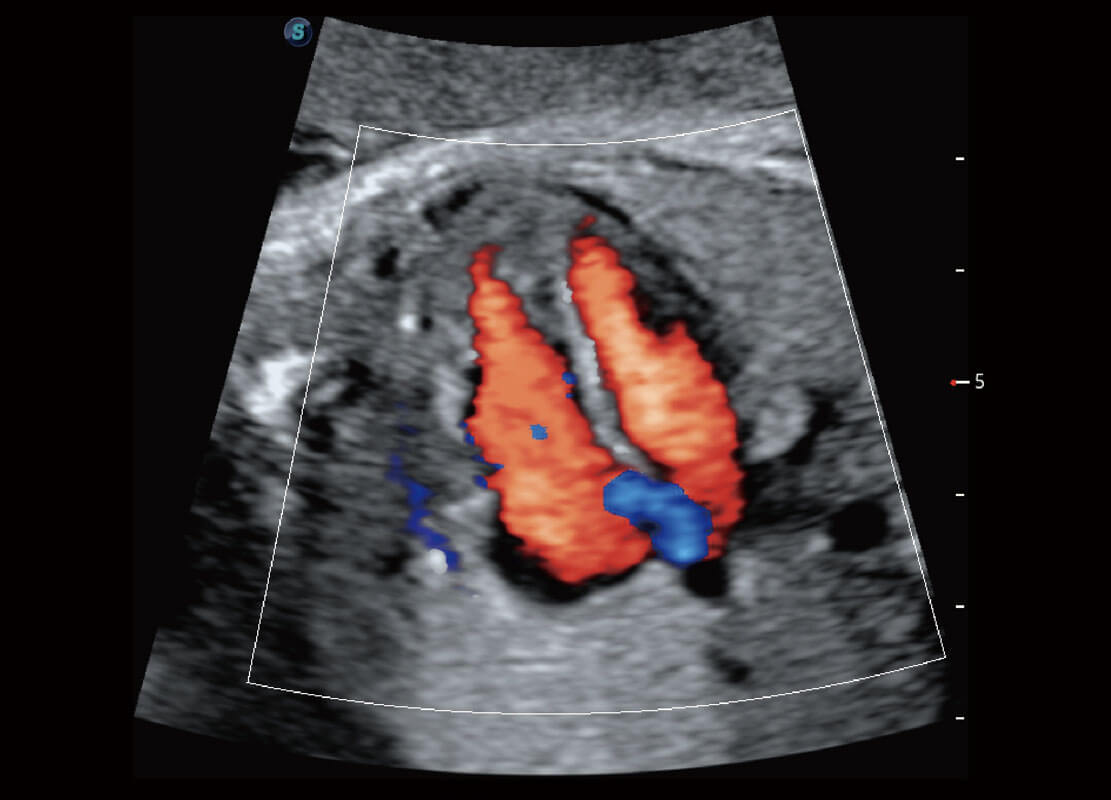

P60在胎儿早孕期超声筛查中为您带来优异的图像质量。

早孕-胎心

胎儿体循环

光影成像-孕囊